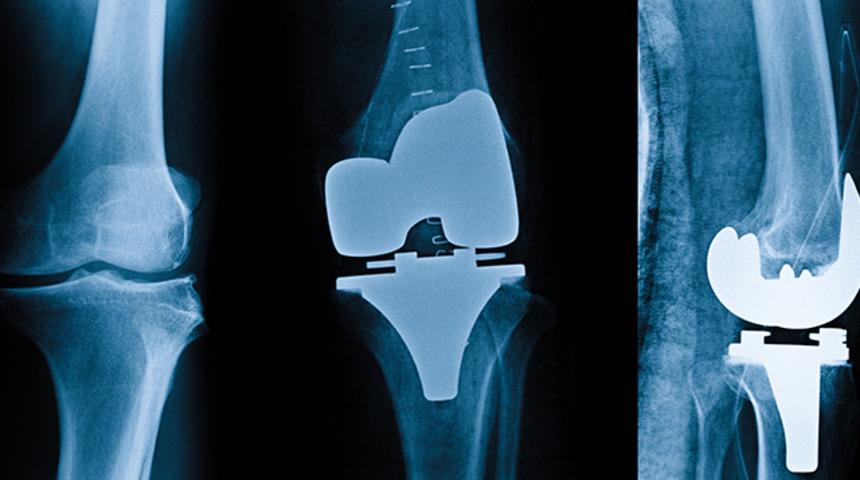

Diz eklemi, birbiriyle eklem yapan 3 farklı eklem yüzeyinden oluşan kompleks yapılı bir eklemdir. Diz ekleminin bütün yüzeyleri, tek bir boşluk içerisinde yer alarak eklemin bütününü oluştururlar. Diz eklemi, her 3 yüzeyinin de uyum içerisinde hareket etmesiyle bir bütün olarak fonksiyon görmekle beraber, her yüzeyin bu bütünlük içerisinde bir görevi vardır. Mesela eklem iç kısmı daha çok dizin rahat bir şekilde bükülmesi ile ilgili iken, eklemin dış kısmı üzerinde hafif dönme hareketlerini gerçekleştiririz. Dizin 3. eklem yüzeyini oluşturan, diz kapağı ile uyluk kemiği arasındaki kısımda ise merdiven çıkma, çömelme gibi aktiviteleri gerçekleştiririz.

Kireçlenme hastalığı, diz eklemindeki 3 eklem yüzeyindeki kıkırdağı etkileyebilen bir rahatsızlıktır. Bu hastalık bazen eklem yüzeylerinin hepsini eşit olarak tutabilirken, sıklıkla 3 eklem yüzeyinden sadece 1 veya 2 tanesinde hastalık bulguları görülmektedir.

Total diz protezi ameliyatı, eklemin bütün yüzeylerinin kaplandığı, yani değiştirildiği bir ameliyattır. Kısmi (Unikondiler) protez cerrahisi uygulanmaya başlanmadan önce, eklem yüzeylerinden sadece bir tanesi etkilenen hastalarda bile bütün eklemin değiştirildiği total diz protezi tedavisi yaygın olarak uygulanmaktaydı. Bir nevi, eklemin hasarlı kısmının tedavisi için sağlam kısmı da kaplanmak zorundaydı. Özellikle, nispeten genç yaşlarda, kireçlenme hastalığının sıklıkla eklemin bir bölümünü tuttuğunun, eklemin diğer kısımlarının ve eklem içerisinde yer alan çapraz bağlarının etkilenmediğinin anlaşılmasından sonra kısmi diz protezi cerrahisi tanımlanmıştır.

Özellikle erken yaştaki hastaların, diz eklemindeki bölgesel kireçlenme hastalığının tedavisinde kullanılan kısmi diz protezi cerrahisi sayesinde, eklemin bağ dengesi ve biyomekaniği aynı normal bir dizdeki gibi korunabilmektedir. Bu cerrahi sonrasında, dizin tamamen katlanabilmesi mümkünken, her türlü sportif faaliyete de izin verilebilir. Özellikle son yıllarda, kullanmaya başladığımız Robotik Cerrahi teknikle, kısmi diz protezi cerrahisini birleştirdiğimizde, sonuçlar da hem hekimler hem de hastalarımız için çok yüz güldürücü olmaktadır.